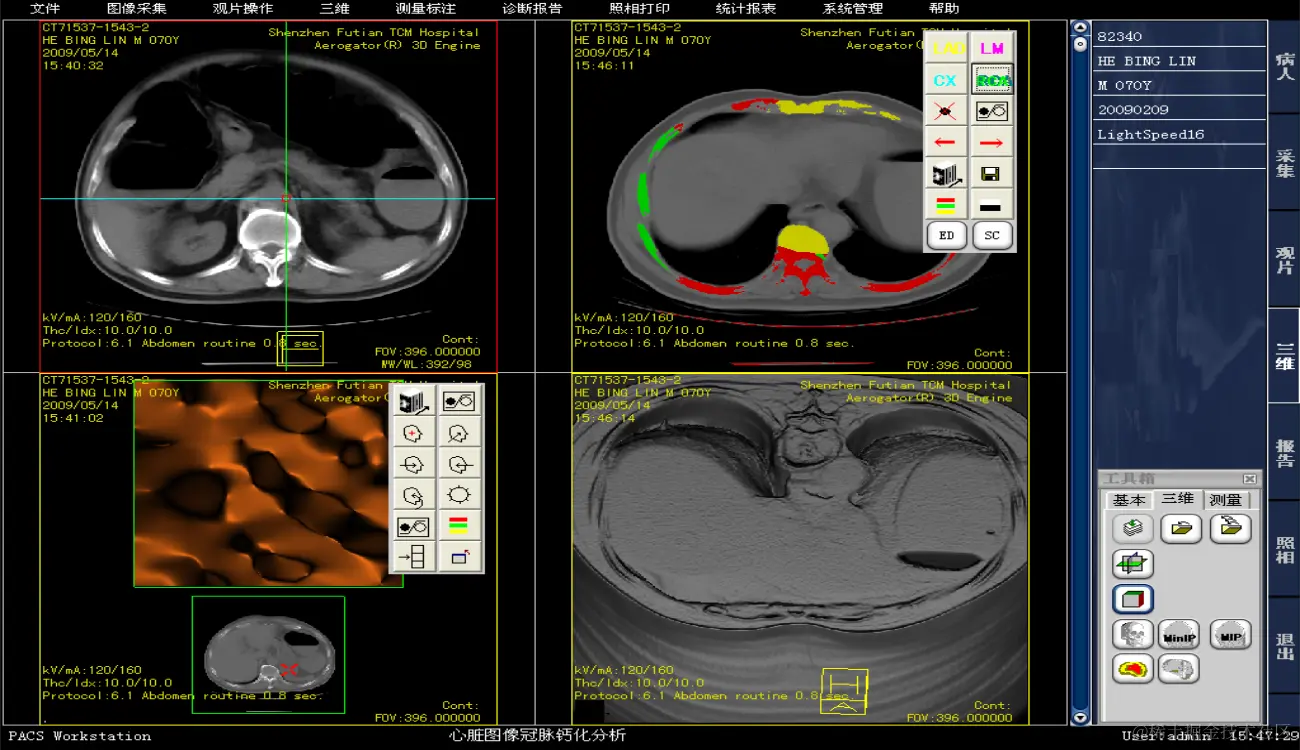

运维级医院PACS系统有源码,有演示,带使用手册和操作说明书 ,开发环境:VC + MSSQL

PACS系统可实现检查预约、病人信息登记、计算机阅片、电子报告书写、胶片打印、报表统计、数据备份等一系列满足影像科室日常工作的功能,并且由于影像数字化存储,用户可利用影像处理与测量技术辅助诊断、方便快捷地查找资料或利用网络将资料传输至临床科室,还可与医院HIS、LIS无缝连接。集成专业三维影像后处理功能,包括:三维多平面重建、三维容积重建、三维表面重建、三维虚拟内窥镜、最大/小密度投影、心脏动脉钙化分析等。